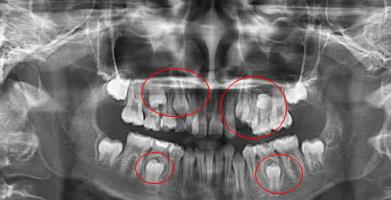

看全景片一般是可以看出有無蛀牙,蛀牙情況嚴(yan) 重與(yu) 否?有無多生牙,牙床是否有沒有萌出的牙胚,是否需要拔除?牙槽骨情況好不好?智齒有幾顆,位置如何,有無對咬牙,是否造成鄰牙齲壞?以及的全口牙齒是否有中線不齊,牙齒咬合不好,牙齒擁擠或稀疏等情況?還有牙齒缺失幾顆,是否有殘根需要拔除,是否需要植骨,需要怎麽(me) 製定種植牙方案以及治療方案。